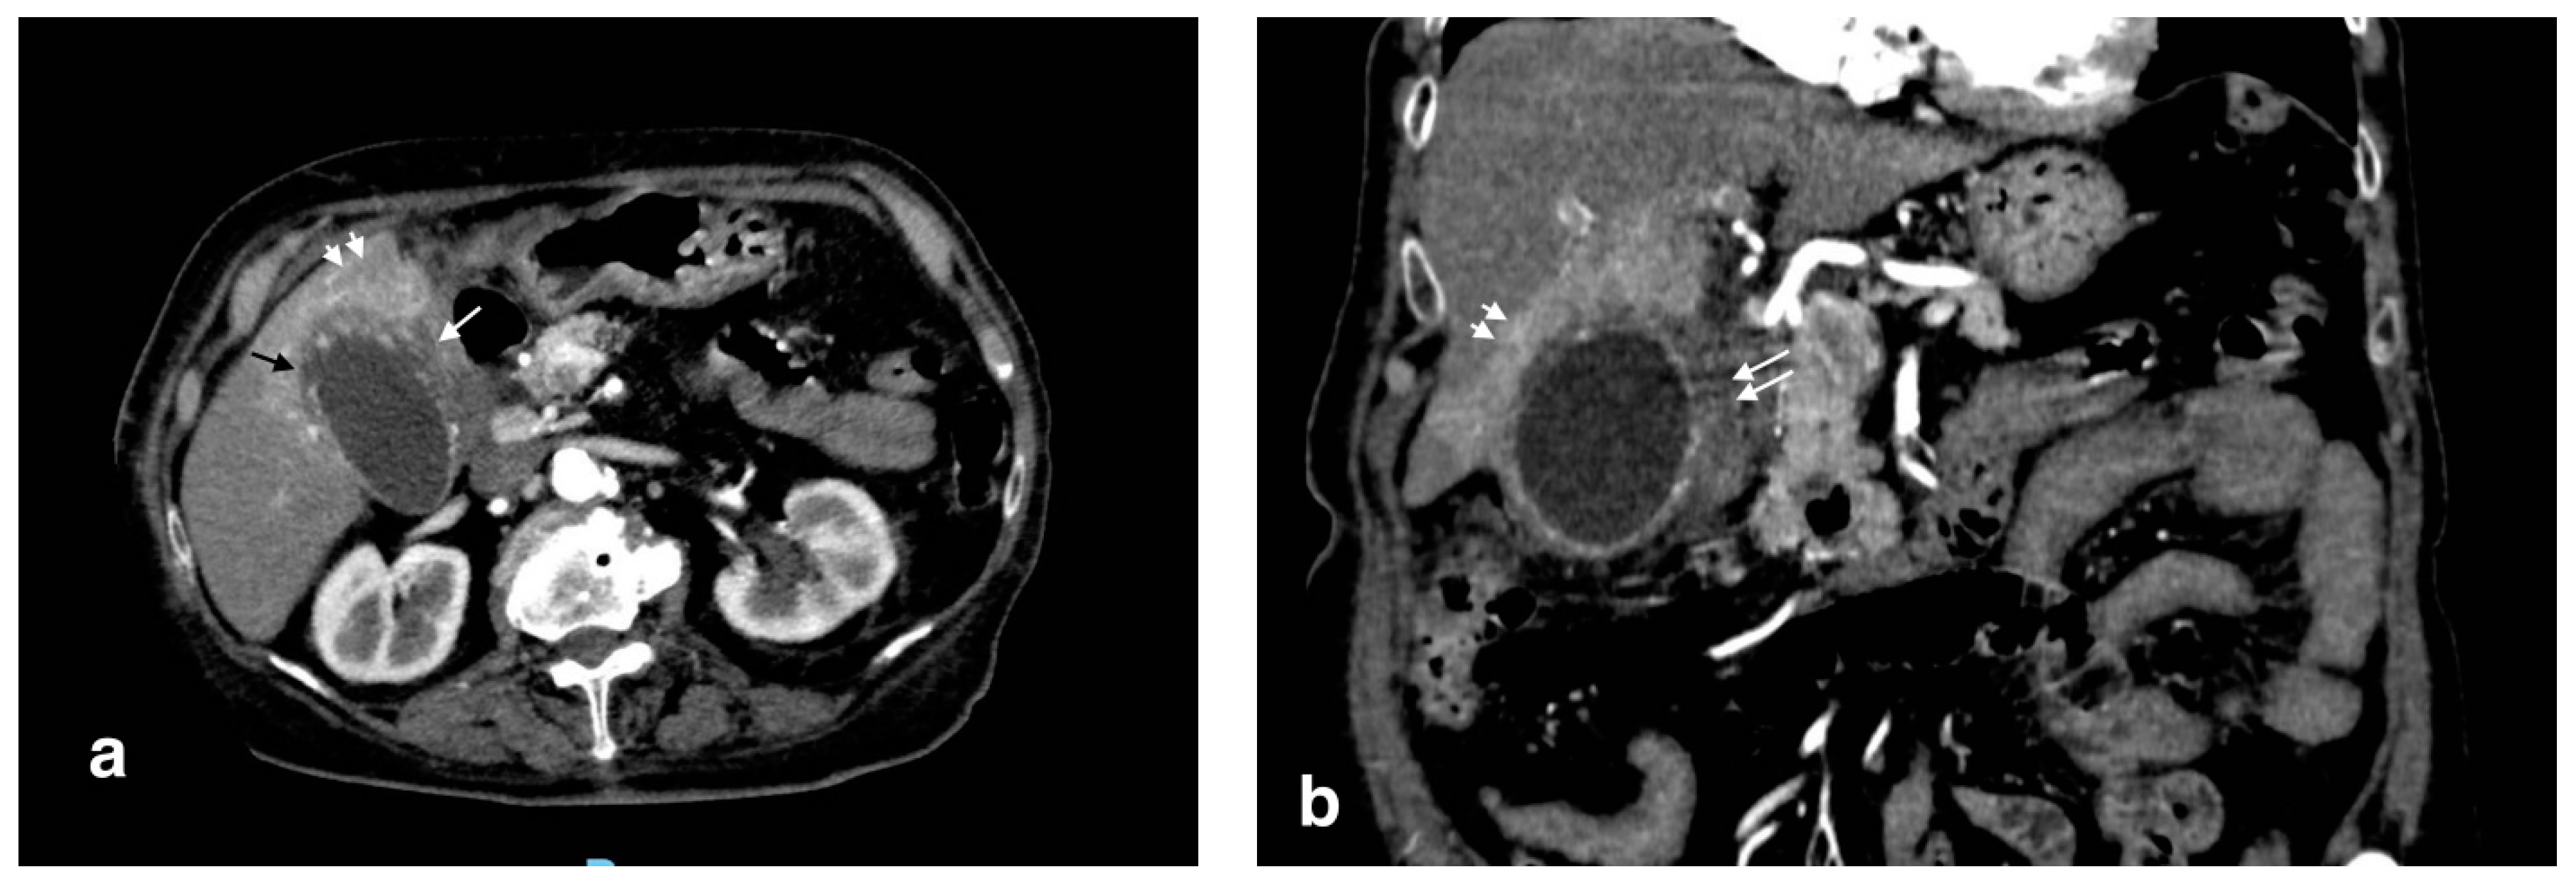

Figure 2.

Gangrenous cholecystitis: irregular wall thickening with bulging and focal defects in the gallbladder wall (black arrows, (a)). Coexisting hepatic hyperemia (arrowheads) and pericholecystic fluid (white arrows) (a,b).